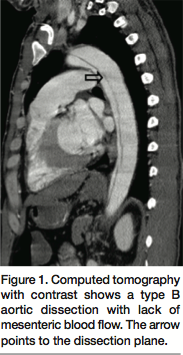

At this time, we decided to perform an exploratory laparotomy and the abdomen was opened. There was no free fluid in the abdomen. The small bowel appeared to be somewhat compromised, particularly in one segment. The base of the superior mesenteric artery was identified and encircled. A micropuncture needle was used and access was obtained with a 0.035˝ wire into the true lumen. A vertebral catheter was then inserted and confirmed to be in the true lumen. We proceeded to use an 8 mm x 4 cm balloon expandable stent Express LD (Boston Scientific, Natick, Massachusetts). The origin of the SMA and the junction between the true lumen and false lumen underwent stent angioplasty. In addition, a 7 mm x 8 cm, self-expandable Sentinel stent (Boston Scientific) was deployed with much of it into the abdominal aorta (Figure 2). Repeat angiogram revealed excellent flow into the SMA and a strong pulse was palpated. A 5-0 Prolene suture was used to close the arteriotomy in the SMA. The patient returned to the operating room after 48 hours for a second look operation and the bowel was healthy. He made an uneventful full recovery and was doing well at his 3-month post-operative visit.